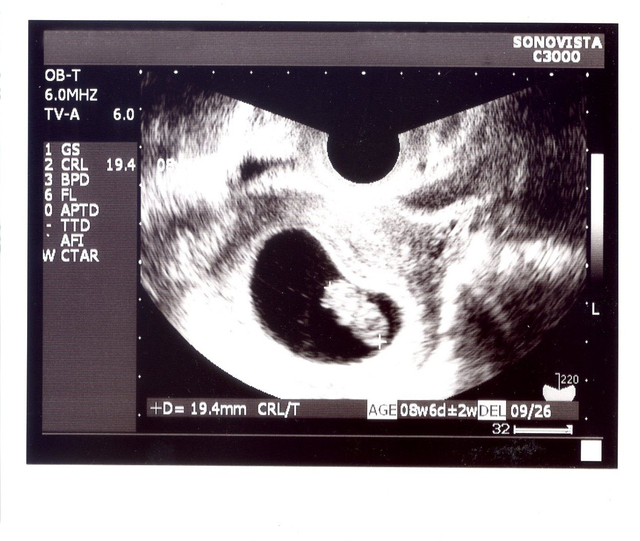

GS はなに?

GSは、胎嚢の大きさをあらわす記号。Gestational (妊娠)Sac(袋) Diameter(直径)の略号となっています。

胎嚢は妊娠初期の超音波検査で、妊娠しているかどうかを確認するための項目の一つとなります。

CRLはなに?

CRLは 頭殿長(とうでんちょう)をあらわす略号。Crown(頭頂) Rump(お尻) Length(長さ)の頭文字をとったものです。

胎児の頭の先からお尻までの長さをあらわすもので、赤ちゃんの身長、とも言える数値になっています。妊娠初期は個体差の少ない妊娠初期に、この長さを測って出産予定日を確認します。